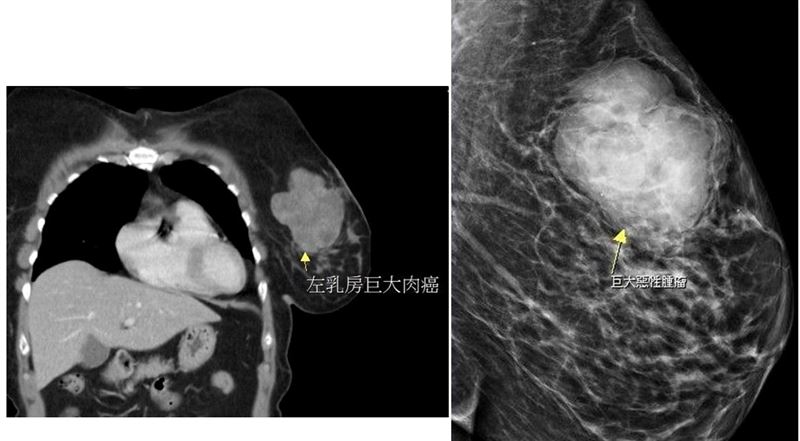

大千綜合醫院外科部馮啟彥主任安排超音波檢查,發現在黃女士的左邊乳房有一個將近10公分大的腫瘤,原以為只是一般常見的乳腺癌,但是手術切除後,經病理報告發現,竟然是非常罕見的肉癌!

此次病人的腫瘤非常大,也大幅增加治療的困難度,所幸手術後病人恢復良好,病理報告也證實腫瘤已切除乾淨,目前持續密集追蹤狀況。馮啟彥醫師提醒,若發現身體有異狀,務必要提早就醫,才能讓治療更加順利。